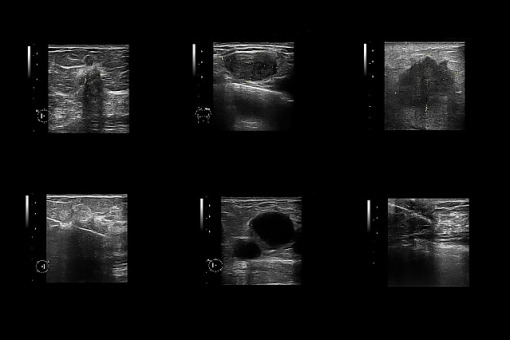

– Dzięki połączeniu dwóch metod analizy obrazu udało się opracować metodę oceny gruczołów sutkowych u myszy, która mogłaby pomóc także w mammograficznej diagnostyce raka piersi u kobiet – informuje „American Journal of Pathology”.